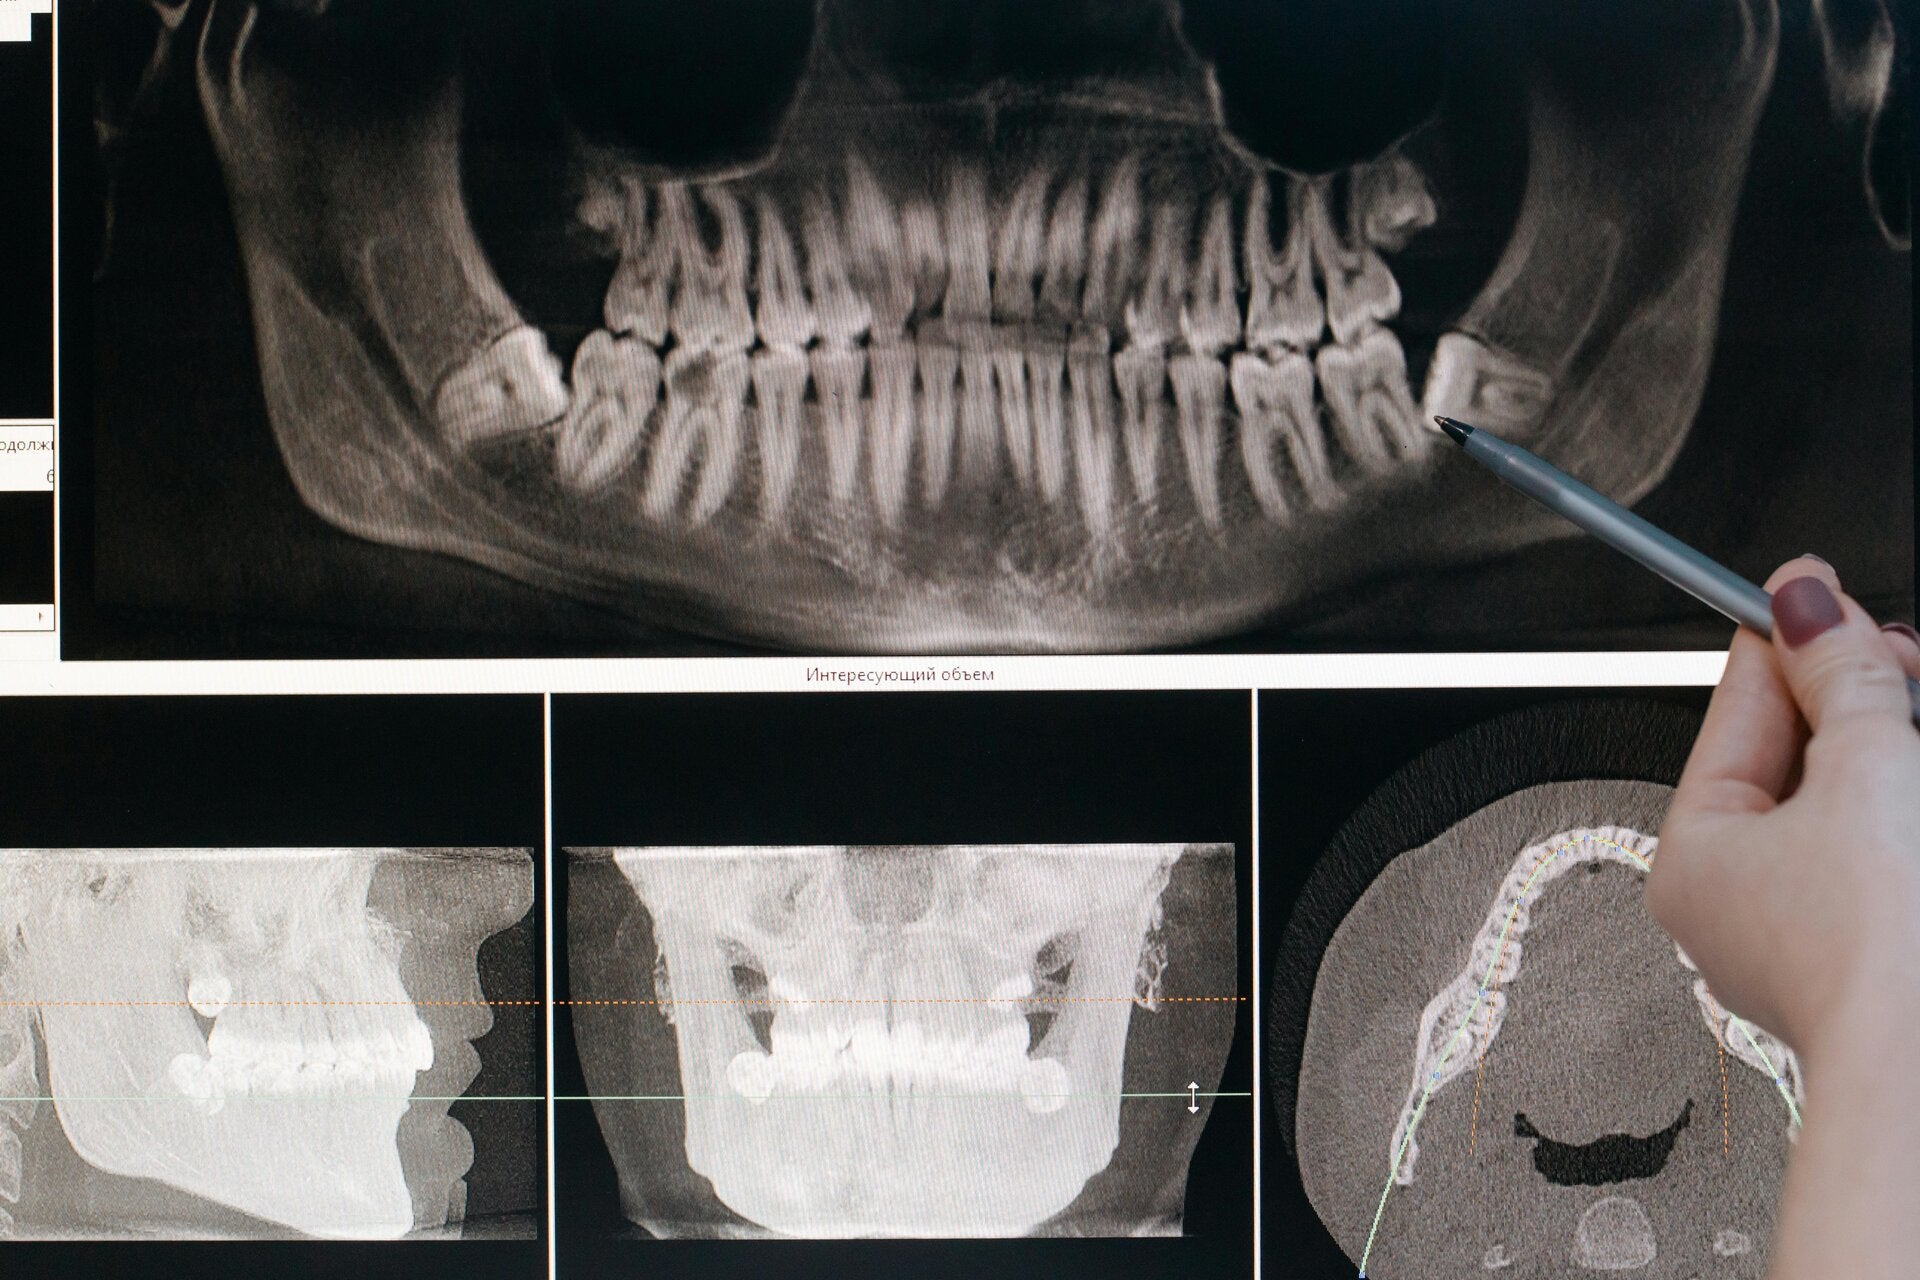

Nowoczesna diagnostyka i bezpieczeństwo

Każdy zabieg poprzedzamy dokładnym badaniem klinicznym i obrazowym.

Dzięki temu plan leczenia jest zawsze dopasowany do indywidualnych potrzeb pacjenta i minimalizuje ryzyko powikłań.